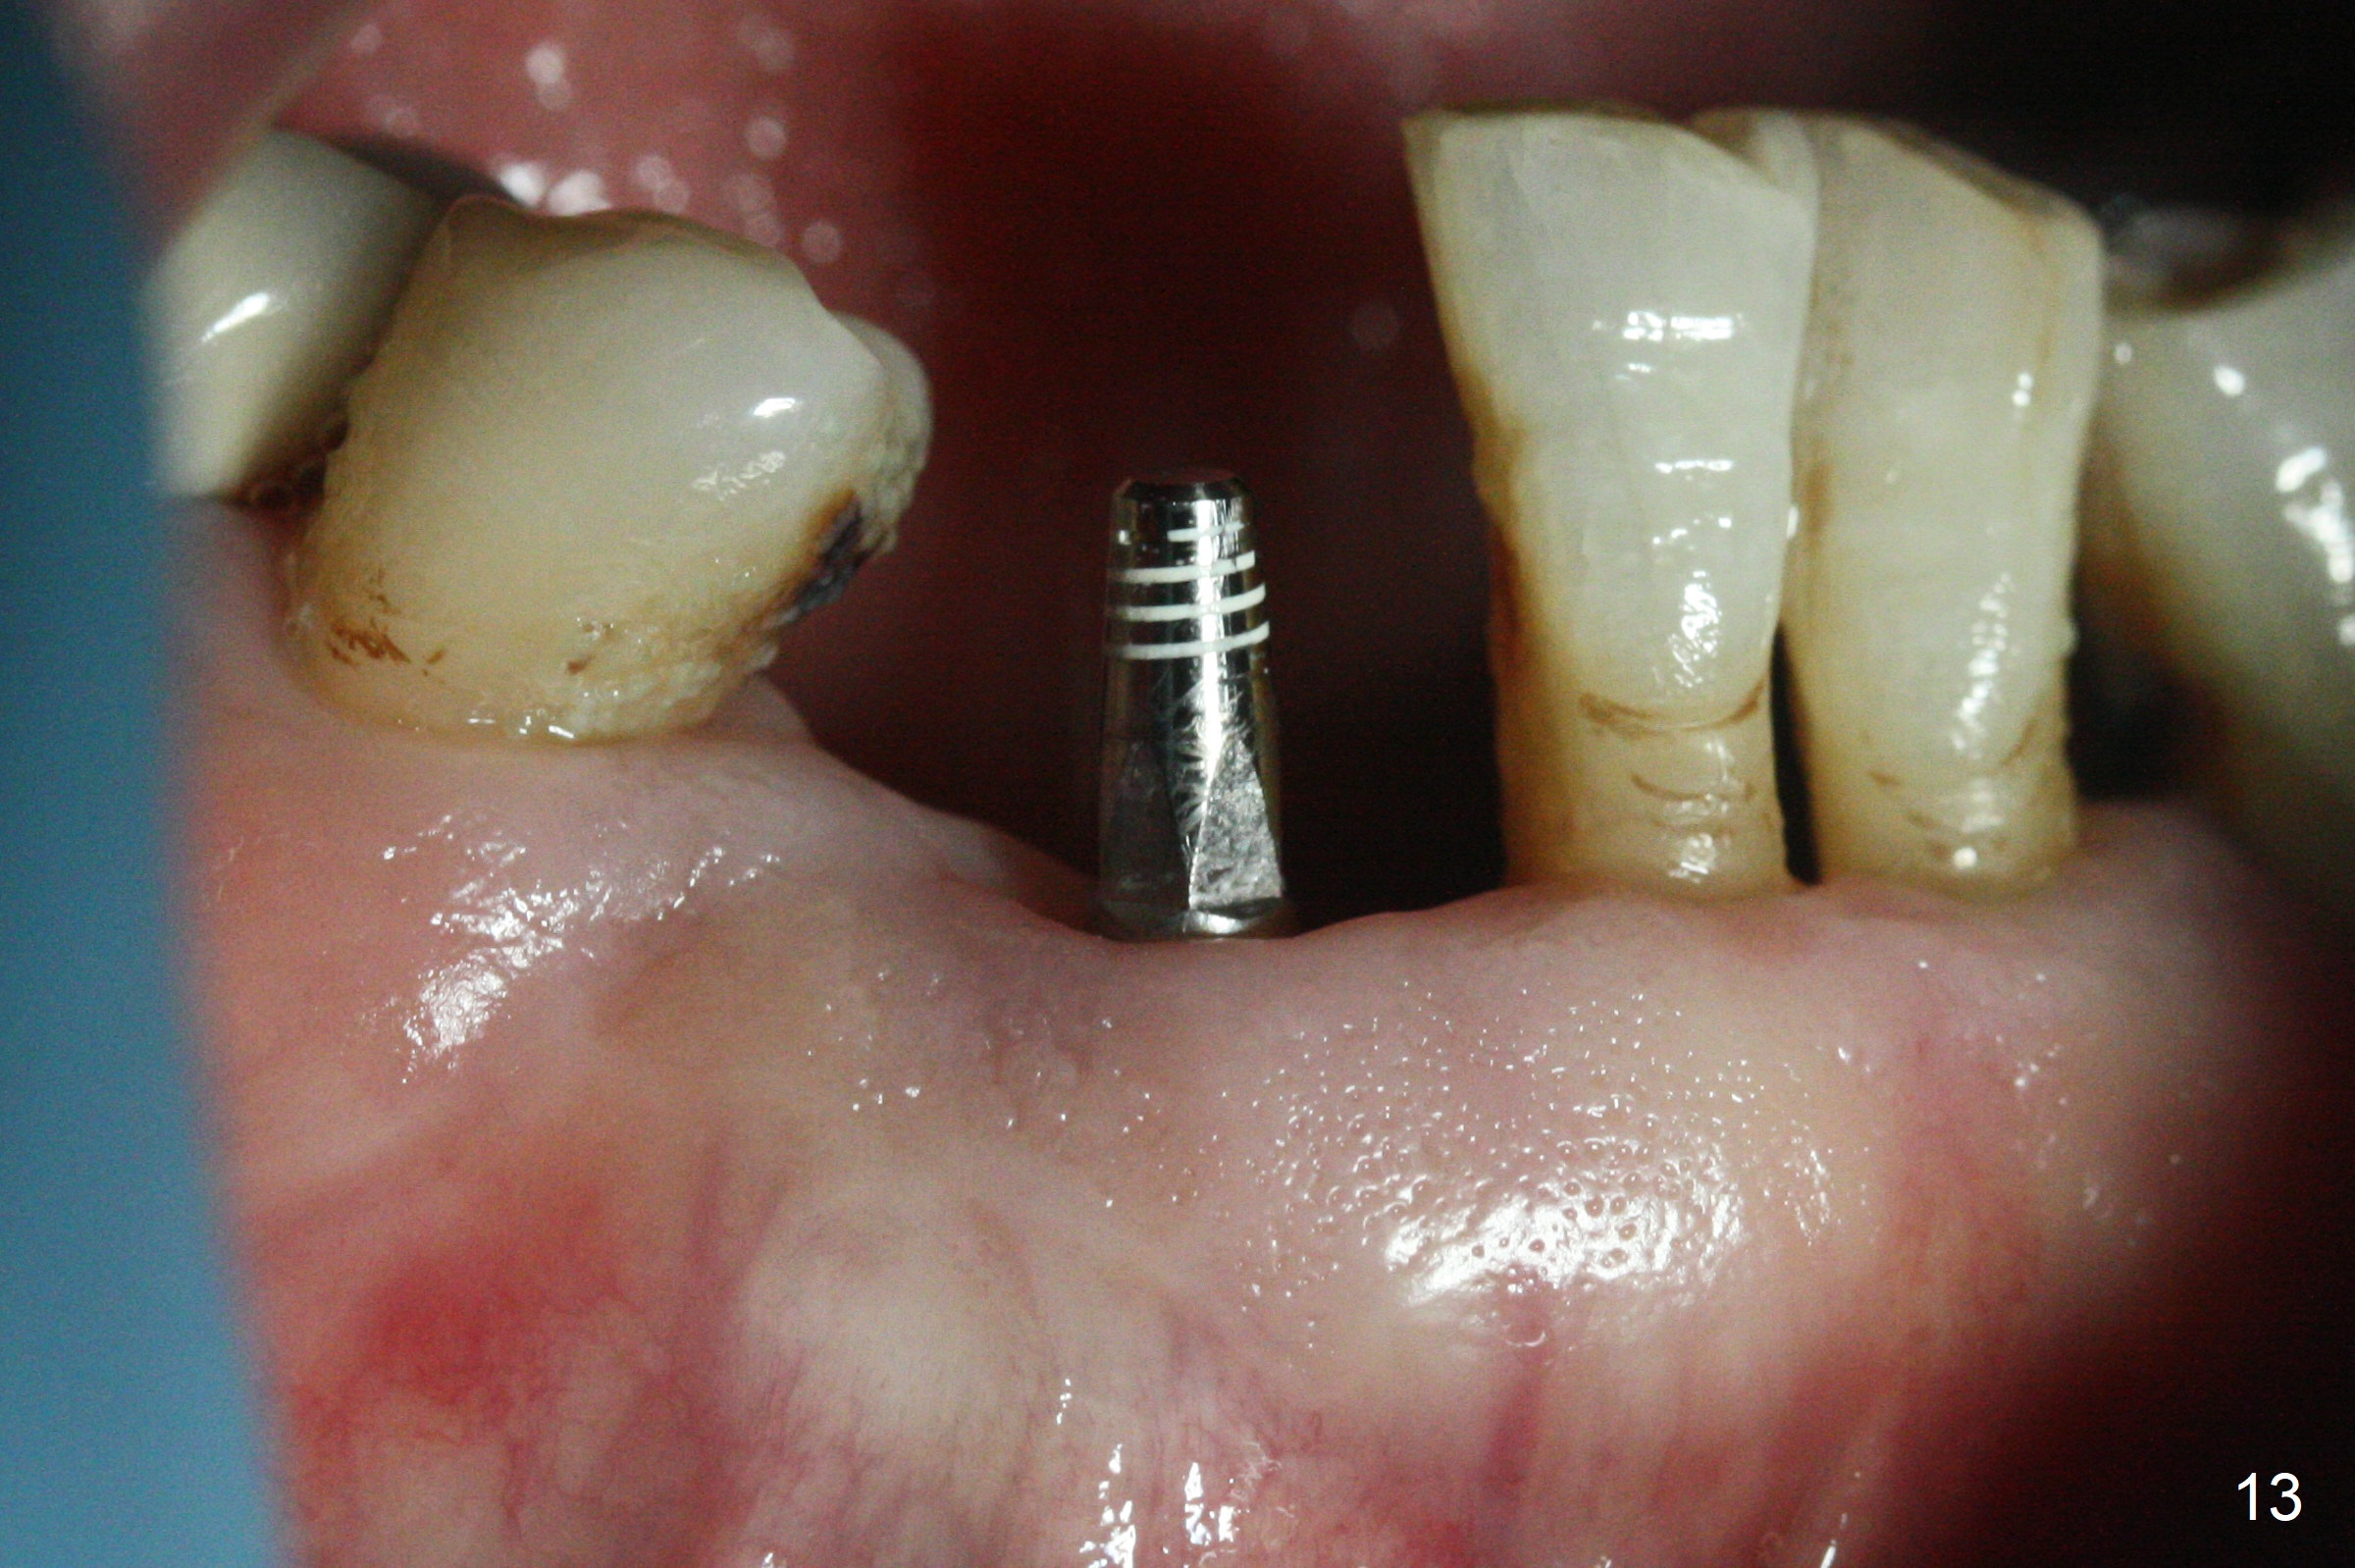

The lower dentition is special, consisting of a residual root (Fig.1 ^), 2 incisor (I), 1 canine (C), 1 premolar (P) and 1 molar (M). The residual root looks like an incisor with rotation of 90º (Fig.2,3). Osteotomy is initiated (Fig.4) for a 3x16(2) mm 1-piece implant (Fig.5 with 45 Ncm). The implant is being placed as distal as possible (Fig.4 arrow) so that a large canine-like provisional is to be fabricated in the large edentulous space (Fig.8,9) after bone graft (Fig.6,7 *). The gingiva around the provisional (Fig.10 P) remains healthy 11 days postop with occlusal clearance against the opposing dentition (Fig.11). The implant threads are not exposed with the help of bone graft 3 months 1 week postop (Fig.12). The gingiva around the implant is healthy (Fig.13). Soft tissue socket is formed by the provisional (Fig.14 *).